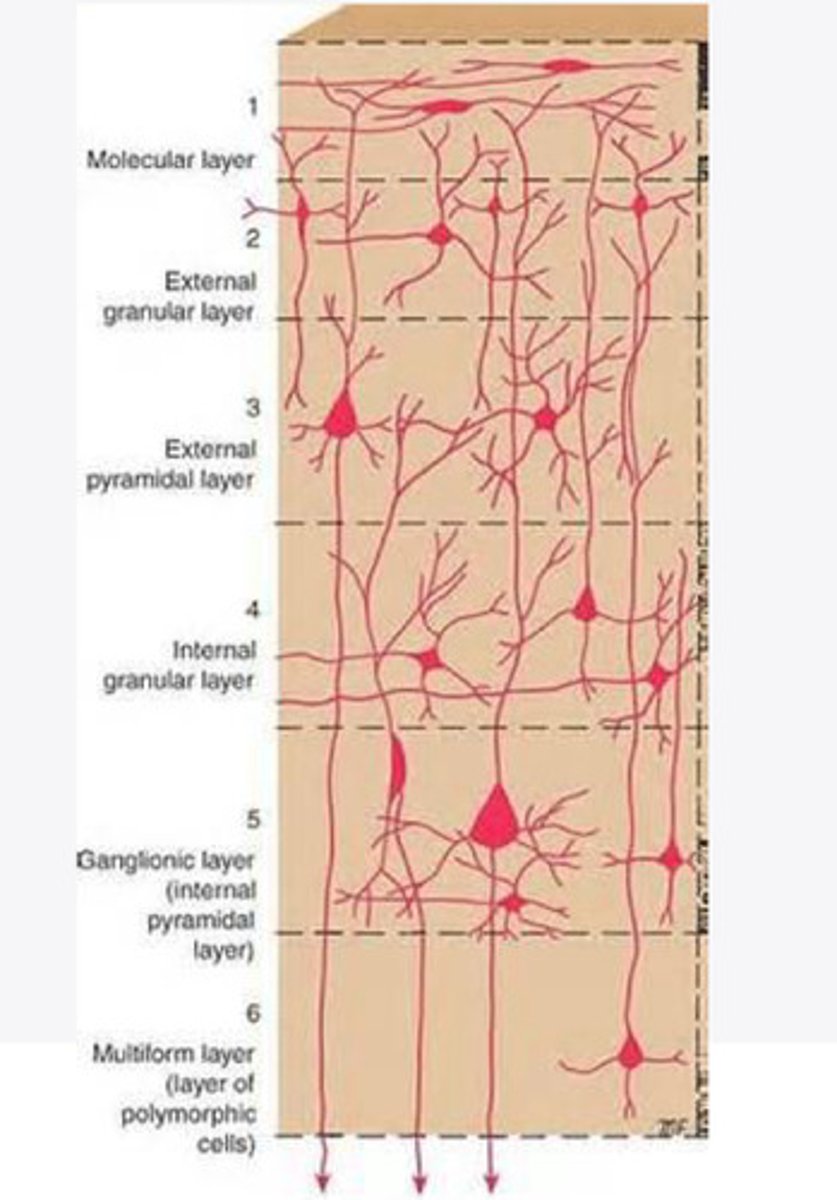

divided into 6 distinct layers, due to varying densities of cell body types within each layer

The cortex of the brain is divided into how many layers? Why is it divided into layers?

Layers of the cortex of the brain pic

2 and 4

What are the layers of the cortex that are associated with input?

3 and 5

What are the layers of the cortex that are associated with output?

molecular layer

What is the name of Layer 1 of the cortex of the brain?

very few cells

Does Layer 1 of the cortex have a lot or few cells?

receives dendrites from internal layers so it may actually function as a coordinating center where layers can communicate action

What does Layer 1 of the cortex do?

1

Every layer sends densities to Layer ____?

1

What layer serves as the "water cooler" of the brain?

external granular layer

What is the name for layer 2 of the cortex of the brain?

receives input from other cortical regions

What is the function of Layer 2 of the Cortex of the brain?

Stellate

What type of cells (stellate/pyramidal) would be most concentrated in Layer 2?

external pyramidal layer

What is the name for layer 3 of the cortex of the brain?

sends output to the other cortical layers

What is the function of Layer 3 of the cortex of the brain?

pyramidal

What type of cells (stellate/pyramidal) would be most concentrated in Layer 3 of the brain?

Layers 2 and 3

What layers are associated with association and commissural fibers?

Layer 3 - axons of cell bodies

Layer 2 - synapse into target areas in Layer 2

What part of the axons is in Layer 2/ in layer 3?

Layer 3 - external pyramidal layer

All axonal cel bodies for association and commissural fibers lie within what layer of the Cortex of the brain?

internal granular

** or called the striate cortex because it is so thick that you can see a line through this layer even in unstrained brain slides

What is the name for the 4th layer of the cortex of the brain?

receives input from the thalamus, geniculocortical layer, and other brainstem areas

What is the function for the 4th layer of the Cortex of the brain?

very thick within the vision, auditory, and somatosensory areas

Is Layer 4 thick or thin within SENSORY areas of the cortex?

Internal pyramidal

What is the name for Layer 5 of the cortex of the brain?

sends axons to the brainstem (corticobulbar) and spinal cord (corticospinal)

What is the function of Layer 5 of the cortex of the brain?

in motor areas of the cortex?

Where is layer 5 very thick in the brain?

the frontal lobe -- very motor heavy

What lobe of the brain will have a thick layer 5 of the cortex of the brain?

the multiform layer

What is the name of layer 6 of the cortex of the brain?

-sends axons back to the thalamus through corticogeniculate fibers

-modulates what information the thalamus sends to the cortex to control the strength of the signal received and modulate what you pay attention to

What is the function of layer 6 of the cortex of the brain?

no

Is layer 6 a motor layer?